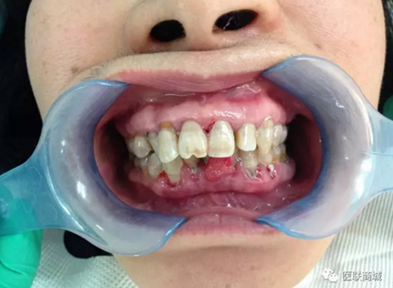

檢查:全口口腔衛(wèi)生差,牙齦紅腫,齦上牙石(+++),齦下牙石(+++),BOP(+),AL為3mm, BI=4,PD大于3mm,下中切牙間唇側(cè)可見如花生米樣大小腫物,碰觸出血,有蒂,基底寬,表面可見充血,下前牙松動(dòng)一度。上下牙列不齊,下前牙間可見間隙。深覆牙合3度。